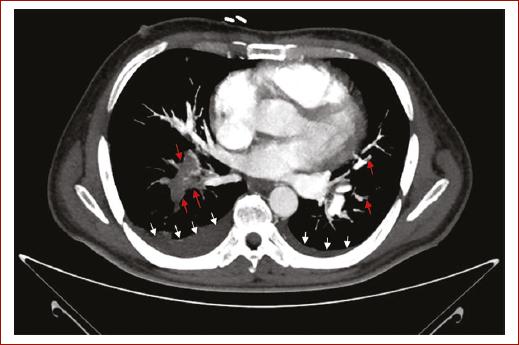

El paciente evolucionó a choque obstructivo extracardiaco e insuficiencia cardiaca aguda, lo que condujo a la decisión de realizar trombólisis con alteplasa 100 mg de forma exitosa en infusión intravenosa durante dos horas según recomendaciones de la guía de la European Society of Cardiology (ESC) para diagnóstico y tratamiento de la embolia pulmonar. Una angiotomografía de tórax posterior confirmó la presencia de tromboembolia pulmonar aguda en diversas áreas pulmonares, incluyendo la arteria lobar inferior derecha y las ramas segmentarias en ambos lóbulos superiores e inferiores y un infarto pulmonar en múltiples lóbulos (Figs. 1 y 2).

Figura 2 La imagen corresponde a una angiotomografía de tórax en fase venosa, realizada bajo protocolo para tromboembolia pulmonar y visualizada en ventana de mediastino. Se observa una tromboembolia pulmonar aguda que compromete la rama basal derecha, así como las ramas segmentarias basales izquierdas de la arteria pulmonar (flechas rojas). Además, se aprecia un leve derrame pleural (flechas blancas).